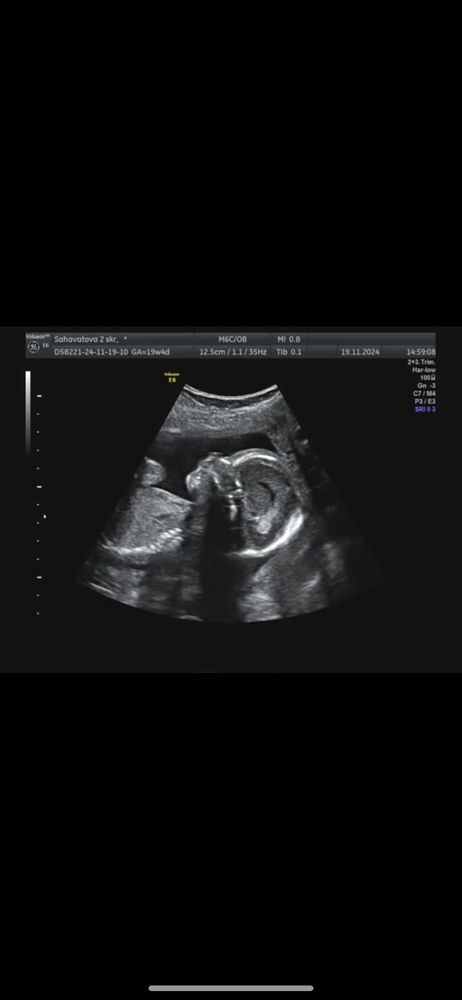

2 скрининг🩷☺️🤰🏼

УЗИ, КТГ, доплерВчера сходила на второй скрининг на сроке 19 недель и 4 дня🩷☺️

Вот такую мы ждём принцессу🥺🥺🥺

Крошка все время сосала свой пальчик и пыталась закрыть личико рукой.

А еще у меня теперь целый диск с фото и видео с УЗИ